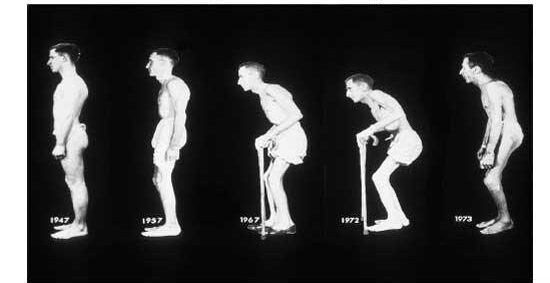

Thời kỳ di chứng:

Thường xuất hiện từ năm thứ 5 của bệnh.

- Dính và hạn chế vận động khớp háng, khớp gối

- Cứng cột sống lưng, thắt lưng và cổ: hạn chế cúi, ngửa, quay, biến dạng gù lưng. Nếu các khớp sườn- đốt sống cũng bị tổn thương thì khả năng giãn nở của lồng ngực cũng giảm, thở sâu khó khăn. Khi đã dính khớp thì triệu chứng đau giảm đi và hết.

- Co rút các gân, teo cơ

– Đặc điểm bệnh nhân VCSDK thường có xu hướng còng lưng, sau đó biến dạng gù cố định do cứng khớp, bởi vậy khi cột sống chưa dính, mục đích chính là duy trì tư thế tự nhiên của cột sống, chống cứng khớp, teo cơ.

- Tập luyện tư thế và dáng đi.

- Giữ tư thế tốt: đầu, thân mình và chân thẳng hàng, mắt nhìn thẳng, ưỡn ngực, vai đưa ra sau, bụng thót lại. Dùng đệm cứng và không dùng gối. Nên nằm sấp